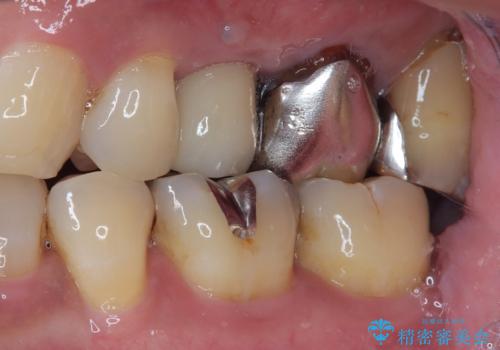

- 頻繁に銀歯が外れてしまうとのことで来院された患者様です。

歯肉の中、深いところまでむし歯が進行しており、歯根を部分矯正で引っ張り出してから補綴治療を行うか、抜歯してインプラント補綴治療を行うか選択することになりました。

海外での勤務があり、部分矯正は困難とのことで、インプラントによる補綴治療を行うこととしました。